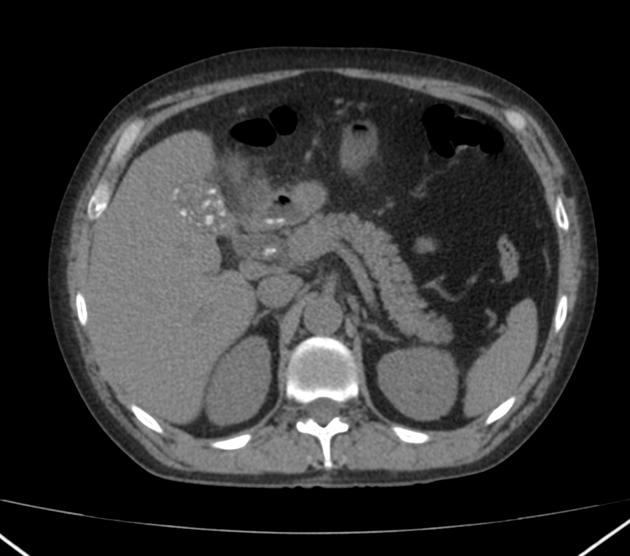

Gallstone Pancreatitis from radiologypics.com

Ct scans can show gallstones, or complications such as infection and blockage of the gallbladder or bile ducts. In addition to detecting gallstones, ct scans can also detect magnetic resonance imaging (mri). A ct scan may be carried out to look for any complications of gallstones, such as acute pancreatitis.

Ct scans are often carried out in an emergency to diagnose severe abdominal pain. However, ct scans also can miss gallstones that you may have. Download as powerpoint open in image viewer figure 4.